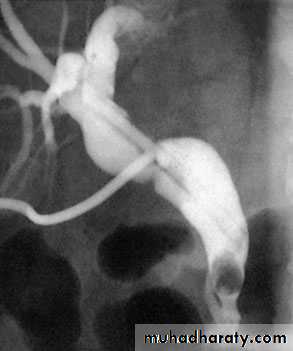

Transhepatic cholangiogram showing a stricture of thecommon hepatic duct

For proximal tumours, percutaneous transhepatic cholangiography is the most useful modality.

PTC

outlines the anatomy of the tumour and the intrahepatic biliary system.

it allows percutaneous biliary drainage,

samples can be obtained for cytology

to confirm the diagnosis.